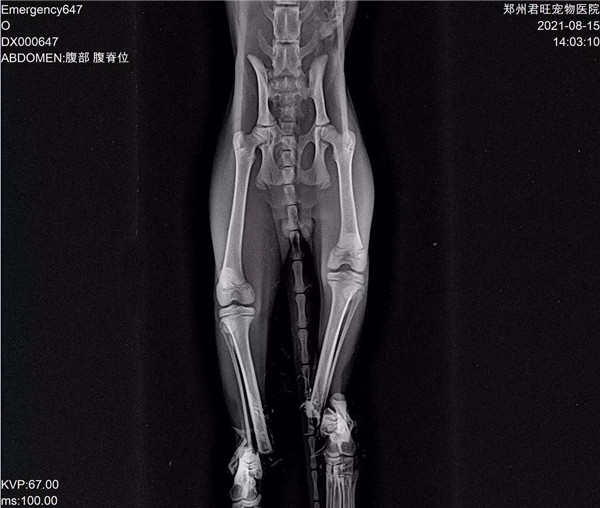

郑州市君旺宠物医院的翟医生,望着眼前面目全非的九福,微微锁起了眉头,简单检查过之后,就得出了判断:九福是被人虐待了。因为它的四条腿均是对称性骨折,两只前腿更是粉碎性骨折,满口牙也被拔掉了。“这绝对不是车祸,或者动物撕咬造成的,只能是人。”

被人折断四条腿、拔掉满嘴牙的“九福”的X光片。 本文图片 猛犸新闻